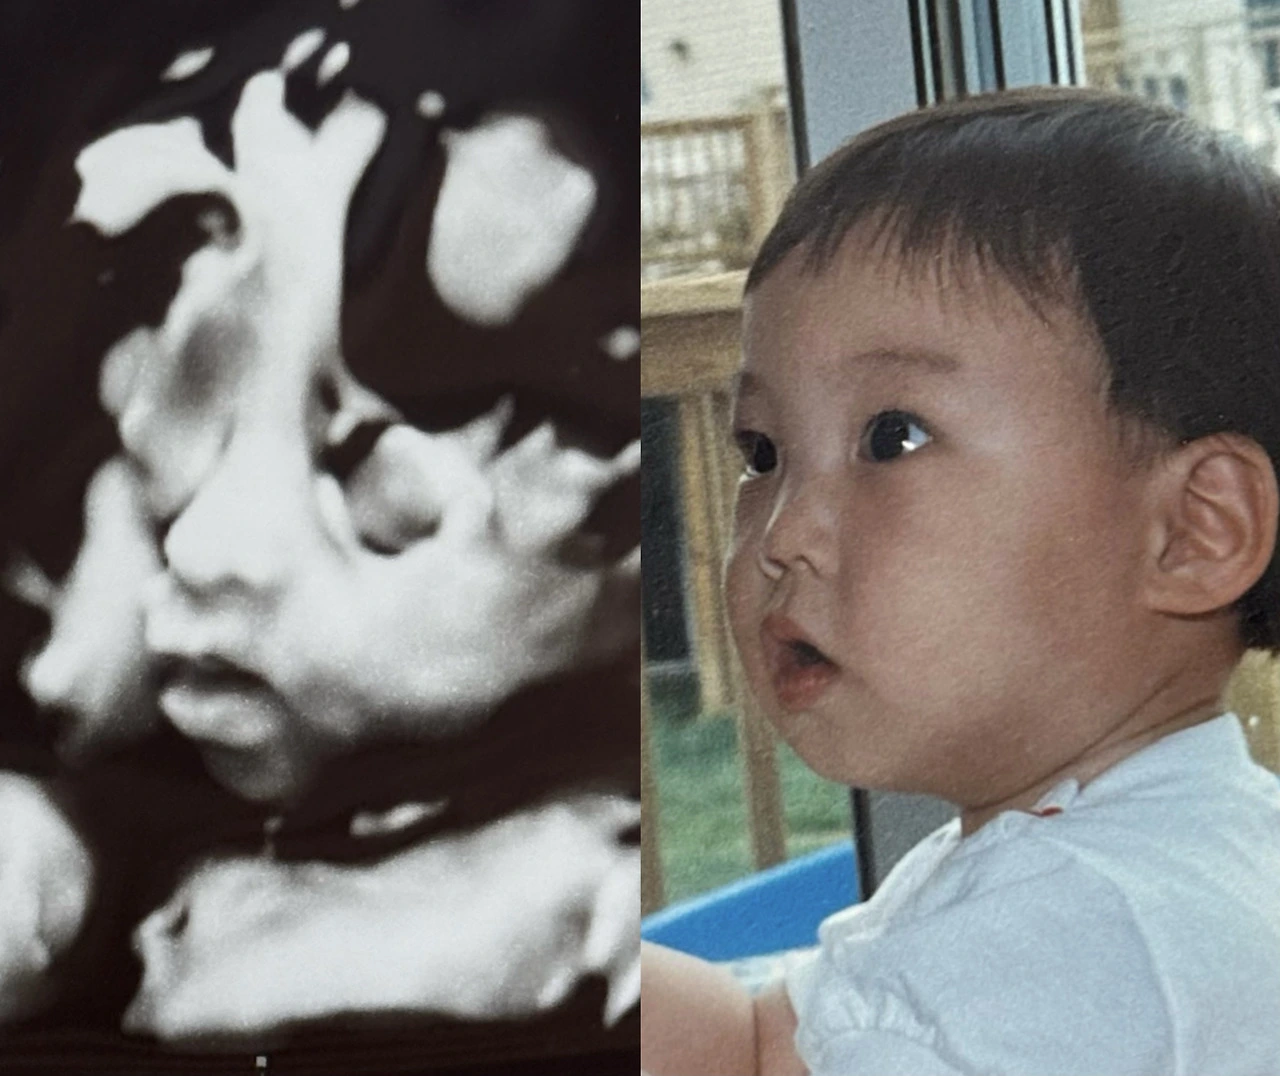

1. 애기 입체 초음파 보기- 코랑 입술만 봤는데도 너무 귀여웠다. 남편 어린 시절 사진과 붙여놓으니 붕어빵!